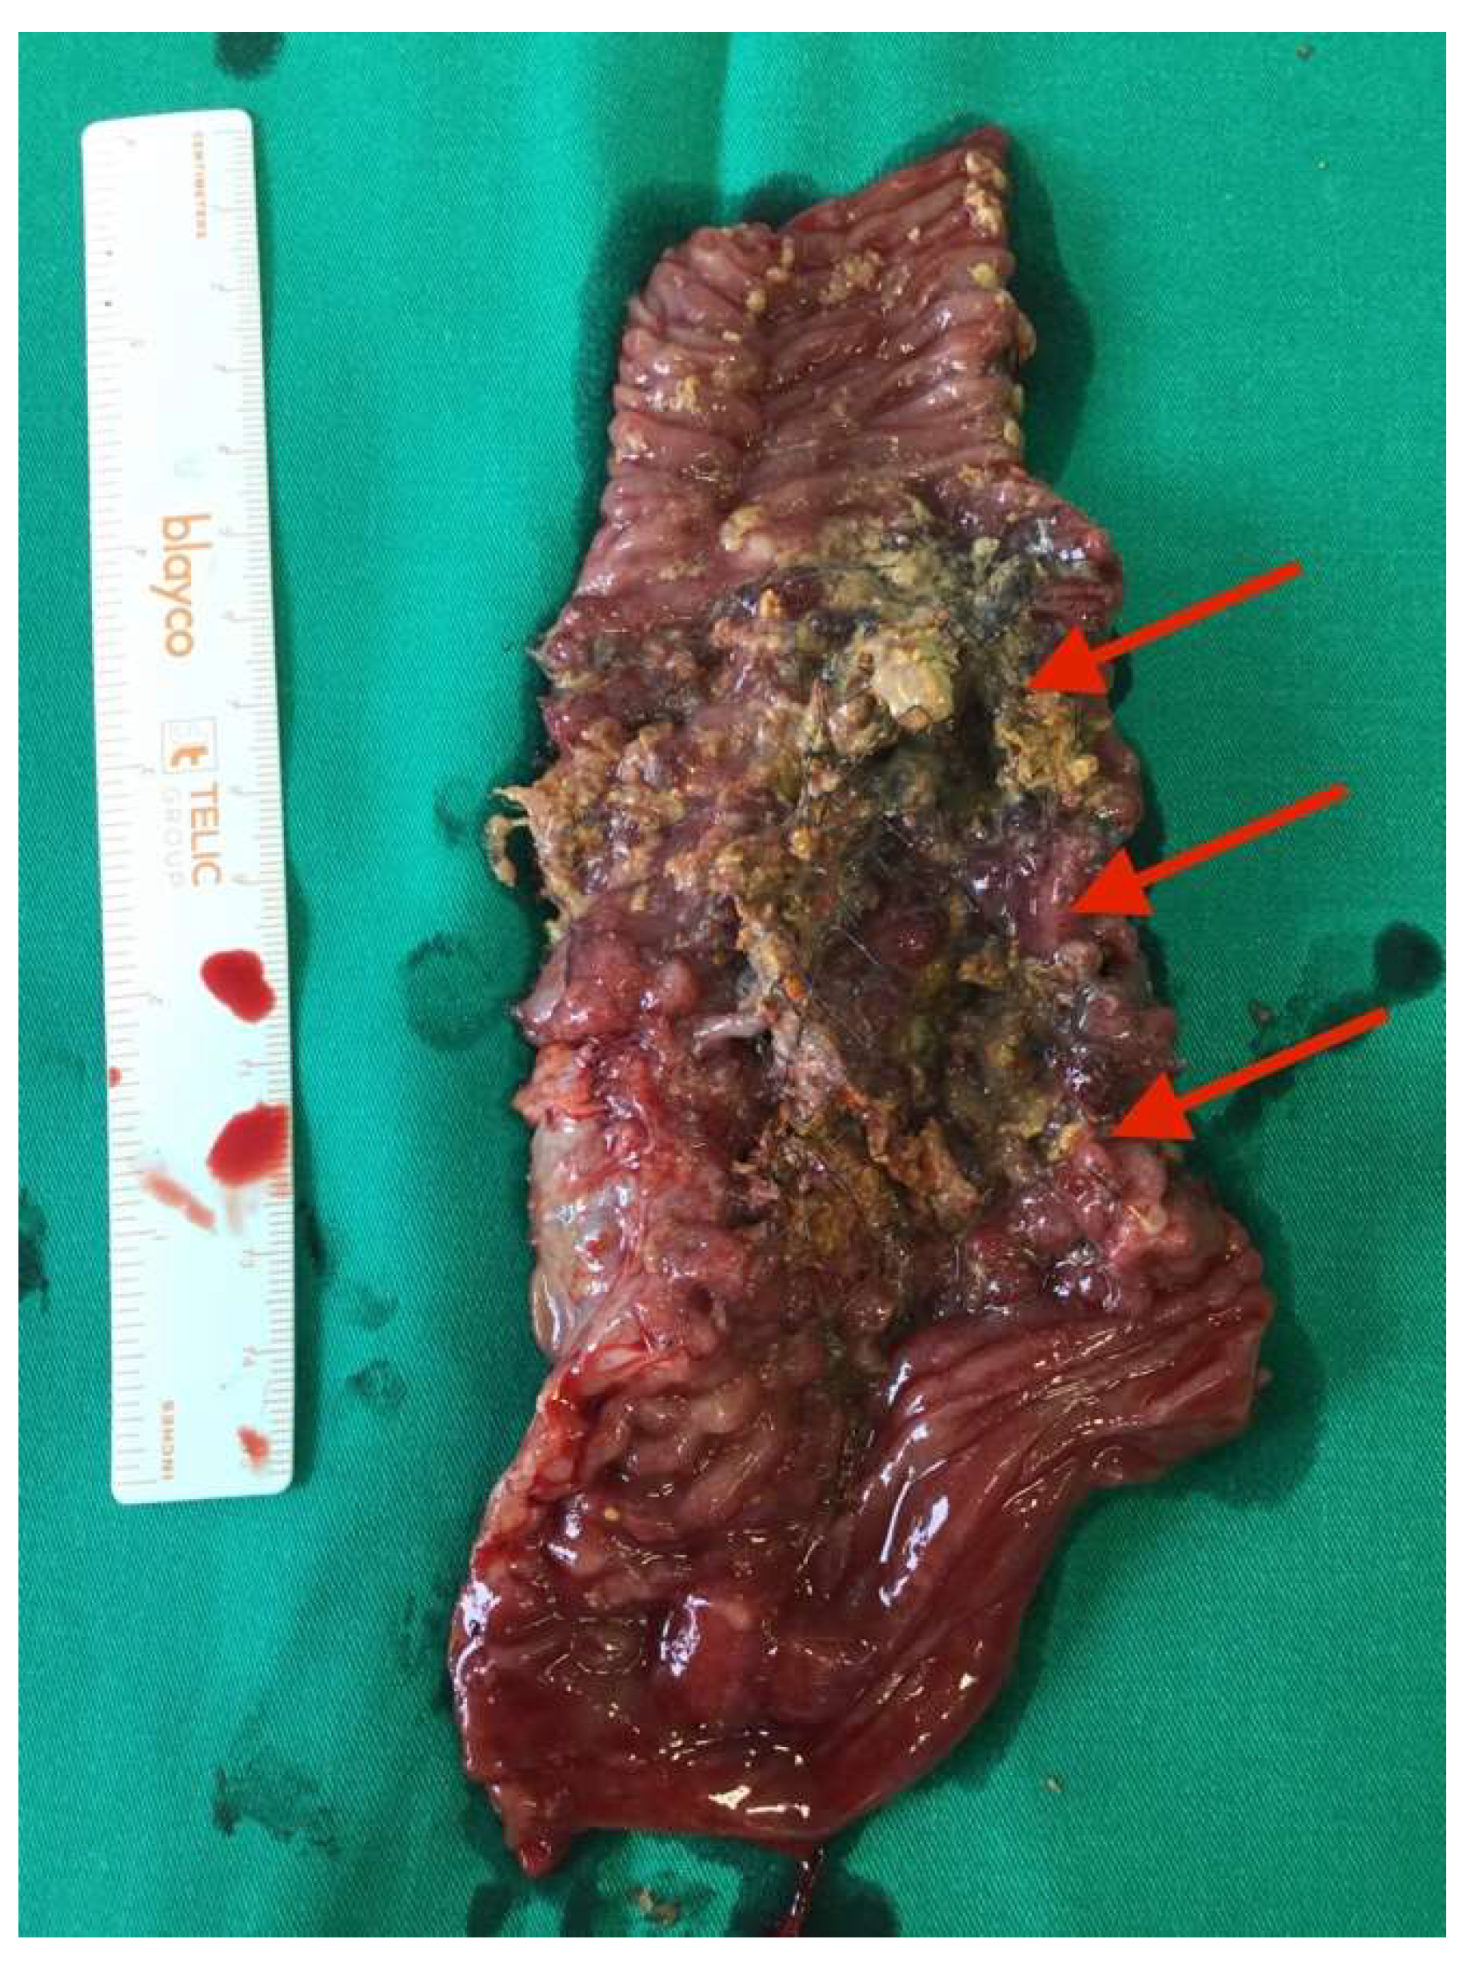

After the optimization of the patient’s nutritional status, a laparotomy, adhaeolysis, and jejunal resection were performed. A conglomerate consisting of the small intestine 80 cm from pl. duodenojejunalis was identified and a metal stent was palpated. The intestines 5 cm proximal to the blockage were found to be hypertrophic and considerably inflated (Figure 2 and Figure 3). The resection of 10 cm of the small bowel with the metal stent was performed and a jejunojejunal anastomosis was formed using a running 3-0 PDS suture (Figure 4).

Figure 3. Enterocutaneous fistula seen in the mobilized small bowel (blue arrow).